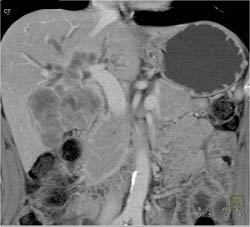

Hemangioma